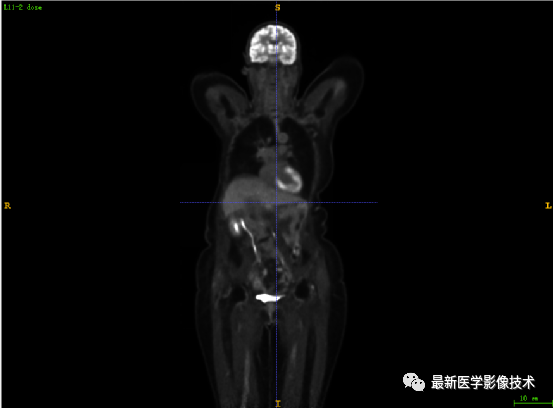

7.1、低剂量2重建结果

第一张是低剂量2的PET图像,第二张是full剂量PET图像,第三张是网络重建的PET图像。